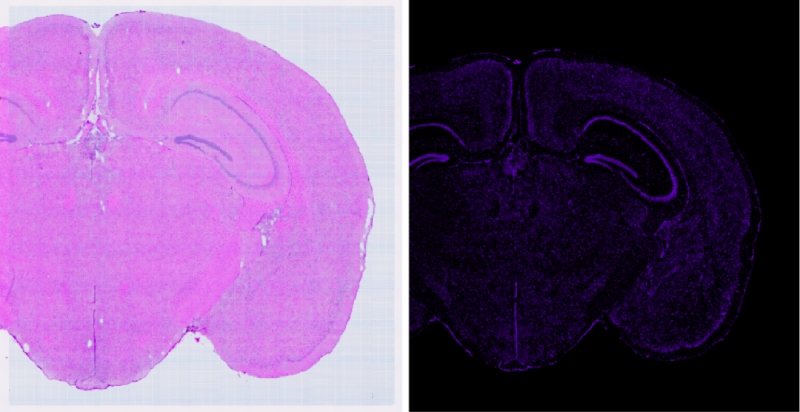

在生命科學的探索之旅中,技術(shù)的每一次革新都是我們深入理解生命奧秘的堅實基石。百邁客生物推出顯微掃描儀領(lǐng)域的旗艦力作——BH1000掃描儀,它將引領(lǐng)我們邁入空間組學成像的新紀元。BH1000掃描儀不僅可以實現(xiàn)人體、動物、植物以及各類玻片標本的快速全切片掃描成像,更以其卓越的性能全面滿足百創(chuàng)空間組學實驗的高端成像需求。其可以實現(xiàn)明場以及熒光的原片高清無錯成像,結(jié)合百創(chuàng)S空間系列細胞分割算法,能夠?qū)崿F(xiàn)精準的空間單細胞分割,為空間組學細胞層面的研究提供了強有力的支持。

通過BH1000快速(20X,8mm*8mm,小于50S)得到高清明場圖像與高清的熒光(支持7個熒光通道,各通道有獨立傳感器,電動切換,標配明場、?DAPI、FITC和CY3)成像結(jié)果來選擇最優(yōu)的透化時間(需要選擇熒光最亮且符合相應(yīng)明場結(jié)構(gòu)無明顯逸散的梯度)

可以利用BH1000對明場及熒光掃描過程中經(jīng)常出現(xiàn)的拼接錯誤進行校準(自主研發(fā)BMCHiper軟件,搭配自研半透半返模塊,實現(xiàn)圖像無錯校準),得到原片無錯高清的熒光圖像與原片無錯高清的明場圖像,為后續(xù)空間數(shù)據(jù)準確的定位和可視化提供基礎(chǔ),使得復雜的轉(zhuǎn)錄組數(shù)據(jù)能夠轉(zhuǎn)化為最直觀,最精準的生物學見解。